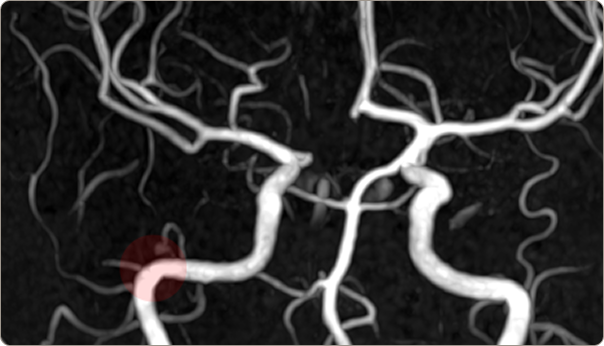

성베드로병원의 MRI 3.0T

MRI(뇌조직)와 MRA(뇌혈관) 촬영 현 최고사양으로 확실하게

성베드로병원의 3.0T MRI는 압도적인 해상도로 뇌 실질의 병변부터 미세 혈관의 흐름까지 한 번에 명확히 찾아냅니다.

MRA

치매, 뇌종양, 뇌경색 등

뇌조직의 정밀 진단